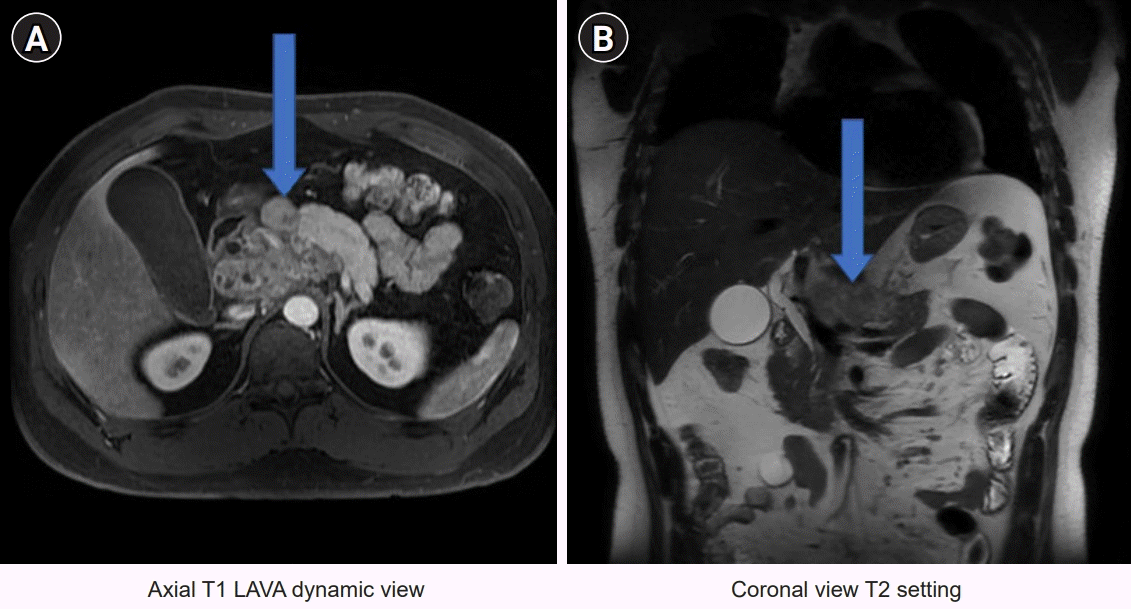

Chest radiography revealed the absence of active lesions. A chest CT revealed no active lesions. Abdominal CT revealed a large mass-like lesion in the pancreatic head and mild dilatation of the common bile duct (CBD). The distal CBD was encased in a mass-like lesion (Fig. 1). Magnetic resonance cholangiopancreatography showed a conglomerated mass with internal necrotic foci and infiltration of the caudate lobe of the liver. Moreover, it shows encasement of the CBD, portal vein, and celiac axis (Fig. 2). The endoscopic retrograde cholangiopancreatography (ERCP) showed a stricture in the mid-CBD. During ERCP, no significant resistance was observed after passing through strictures. Endoscopic ultrasound (EUS)-guided biopsy, brush cytology, and endoscopic retrograde biliary drainage (ERBD) were performed (Fig. 3). Before ERBD insertion, the peak total bilirubin was 6.79 mg/dL. AST and ALT levels were 466 and 801 U/L, respectively. After ERBD insertion, the total bilirubin level decreased to 1.00 mg/dL, and AST and ALT levels decreased to 27 and 65 U/L, respectively, on the 9th day after the procedure. An EUS-guided biopsy confirmed the superficially biopsied bile duct mucosa and benign-looking epithelial cell stripes. The cytological analysis revealed only a limited number of cells.

Fig. 2.

Magnetic resonance cholangiopancreatography images. (A) Axial and (B) coronal views. A conglomerated mass with internal necrotic foci was noted with encasement of the common bile duct, portal vein, and celiac axis (blue arrow).